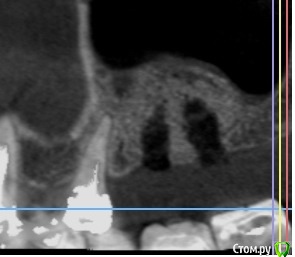

Andre_ Опубликовано 14 июня, 2018 Поделиться Опубликовано 14 июня, 2018 ... в чём дело, сразу не поймёшь.Добрый всем день. Выполнен открытый синус - лифтинг с Bio-Oss, исходно в области альвеолярного отростка высота своей кости 2-3 мм, через 6 месяцев - имплантация без особенностей, ложе умеренно кровило. Гранулы на сверле были, но встали имплантаты с торком порядка 20 Н/см2. Раскрытие спустя 3 мес., имплантаты на фдм выкручены рукой. Ложа откюретированы, заполнены коллагеном и ушиты, спустя 5 суток жалобы на боли - искомая область абсцедирует. Разрез, гной и крупицы, стенки и дно ложа винтов при зондировании инструментом таки твёрдые. Назначены а\б повторно, и загружены фото с контрольной КТ. Где, по- вашему, допустио ошибку и какую? И каков прогноз на переустановку? Столкнулся с такой проблемой впервые и немного дезориентировался. Ссылка на комментарий

TIGER Опубликовано 20 июня, 2018 Поделиться Опубликовано 20 июня, 2018 ... в чём дело, сразу не поймёшь.Добрый всем день. Выполнен открытый синус - лифтинг с Bio-Oss, исходно в области альвеолярного отростка высота своей кости 2-3 мм, через 6 месяцев - имплантация без особенностей, ложе умеренно кровило. Гранулы на сверле были, но встали имплантаты с торком порядка 20 Н/см2. Раскрытие спустя 3 мес., имплантаты на фдм выкручены рукой. Ложа откюретированы, заполнены коллагеном и ушиты, спустя 5 суток жалобы на боли - искомая область абсцедирует. Разрез, гной и крупицы, стенки и дно ложа винтов при зондировании инструментом таки твёрдые. Назначены а\б повторно, и загружены фото с контрольной КТ. Где, по- вашему, допустио ошибку и какую? И каков прогноз на переустановку? Столкнулся с такой проблемой впервые и немного дезориентировался. sav1.jpg sav2.jpg sav3.jpgСверлили под импланты по полному протоколу? Ссылка на комментарий